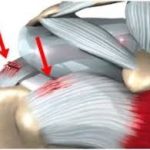

Cervicogenic Headache: When Your Neck Is the Real Cause of Your Headache Understanding Rotator Cuff Tendinopathy: Causes, Symptoms & How Physiotherapy Can Help

Understanding Rotator Cuff Tendinopathy: Causes, Symptoms & How Physiotherapy Can Help